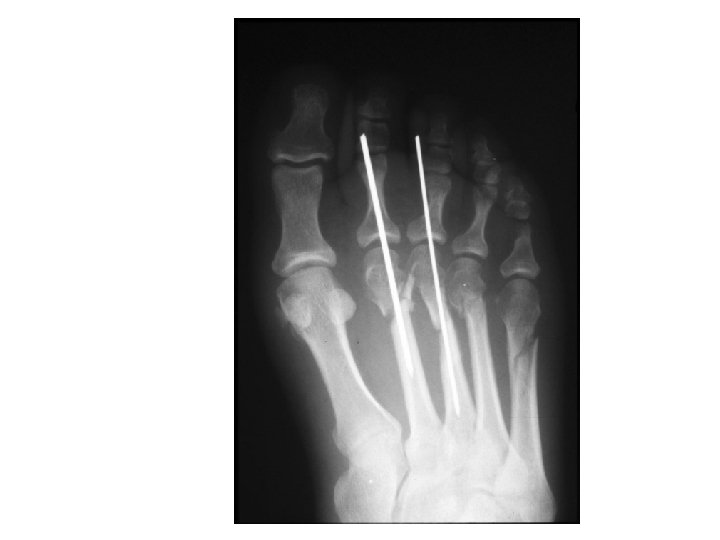

Treatment of Jones Fractures includes several options. Option 1 - immobilization of foot and ankle with non weight bearing for a period of 1 month to 6 plus weeks and more time may be required if the bone healing is delayed. The peroneus brevis tendon attaches at the proximal end of the 5 th Metatarsal and treatment without ankle immobilization is not effective. Every time the muscle contracts and pulls on the tendon, the fracture site is disrupted. This type of fracture is known to form a non union.

Option 2 - insertion of a intramedullary screw into the fracture to compress the fragment and the bones back together. May or may not be used with a bone graft. Many physicians will also opt to use a bone growth stimulator on this fracture to insure that healing occurs. Option 2 is certainly preferred in the authors opinion since the fracture site is stabilized and the ends of the fracture approximated. The screw fixation allows for earlier return to weight bearing and decreased immobilization time. (Dr. Joe Milne, Dr. Steve Brotherton)